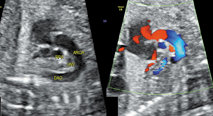

孕妇31岁,孕27+1周,产前常规行胎儿超声心动图检查。既往体健,无传染病及遗传病史,孕期顺利。超声显示:胎儿心脏位于胸腔内,位置正常,心尖指向左前方。心轴及心胸比值正常。各心腔内径比值正常,室壁厚度及运动正常。各瓣膜形态及启闭未见明显异常,彩色多普勒血流显像未见异常血流信号。三血管–气管切面:肺动脉左侧可见管状回声,内径0.21 cm(图1),探头于该切面向胎儿头侧偏转,可见其跨越右肺动脉上方,于主动脉弓下方从左向右径直走行,在距上腔静脉右心房入口约0.61 cm处汇入其中,其内可见静脉频谱(图2)。主动脉弓长轴切面:主动脉弓下方可见两个管状回声,呈"双眼征",其中前下方为右肺动脉横断面,后上方为异常血管断面;彩色多普勒示二者血流方向相反(图3)。余切面未见明显异常。心律规整,心率148次/min。超声提示:胎儿左无名静脉走行异常(主动脉弓下走行)。产后经超声及心血管造影证实。

在胚胎发育的第7周,左、右两侧的前主静脉借血管丛连接成一条斜行的血管,即无名静脉。随着左无名静脉发育形成后,左侧前主静脉和Cuvier管逐渐闭塞,左上腔静脉退化,右侧前主静脉与Cuvier管发育成为正常的右上腔静脉[1]。左、右无名静脉分别接收左、右颈总静脉和左、右锁骨下静脉的静脉血,汇总成上腔静脉,自右房上面注入右房。正常情况下,左无名静脉由左向右斜行跨过主动脉弓上方,汇入上腔静脉。但本例中,三血管–气管切面向胎儿头侧偏转动态扫查显示左无名静脉在主动脉弓下方与右肺动脉上方之间横过主动脉弓,在上腔静脉入右心房处同上腔静脉汇合;主动脉弓长轴切面也可显示主动脉弓与右肺动脉间存在一圆形静脉血管结构,而正常情况下,主动脉弓下仅有右肺动脉的横断面;三血管–气管切面肺动脉左侧可见一管状回声,为静脉频谱,这是由低位走行即主动脉弓下走行的左无名静脉所致。关于三血管–气管切面肺动脉左侧发现异常管状回声,有以下三种可能:①永存左上腔静脉Ⅰ型,左上腔静脉血经冠状静脉窦入右房,此型约占90%以上。超声表现:四腔心观左房室沟交界处见扩张的冠状静脉窦;三血管切面肺动脉左侧出现一静脉血管,呈"四血管"改变,且该静脉频谱与右上腔静脉频谱或肺静脉频谱相似;旋转探头,发现该静脉与冠状静脉窦相连且血流方向与右上腔静脉相同。②完全性肺静脉异位引流心上型,四腔心观看不到正常回流入左心房的4支肺静脉,左心房后方可见异常血管,为垂直静脉;三血管–气管切面肺动脉外侧可见管状回声,但血流方向与右上腔静脉相反,为上行的垂直静脉,先后汇入左无名静脉及右上腔静脉。③伪像,由于切面偏斜,将左房的一部分也包括在其内,若此时观察到4支肺静脉均回流入左心房,即为伪像所致。排除以上几种情况,特别是排除了严重危及新生儿存活的完全性肺静脉异位引流,本研究即可考虑左无名静脉主动脉弓下走行的可能。综上所述,超声表现为三血管–气管切面肺动脉左侧异常管状回声,主动脉弓长轴下方出现"双眼征",且二者血流方向不同,并且无其他心内外结构异常时可以诊断为左无名静脉主动脉弓下走行。